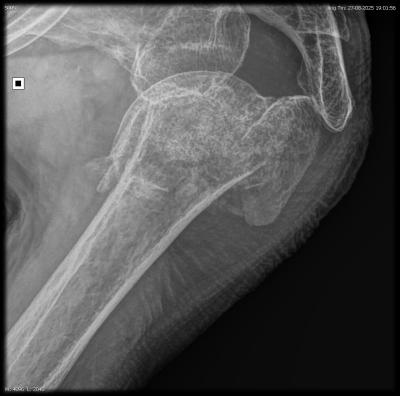

Een goed resultaat schouderbreuk bij 95 jaar Lees meer

schouderbreuk bij 95 jaar schouderbreuk bij 95 jaar